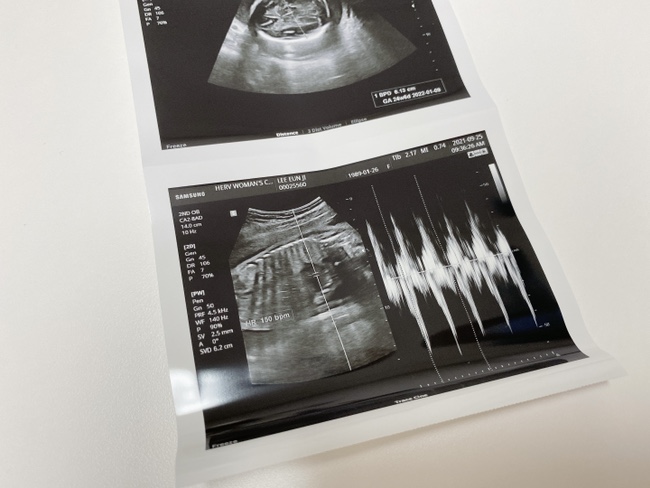

임신일기_25~28주, 입체초음파

임신일기_임신21~24주, 임당검사